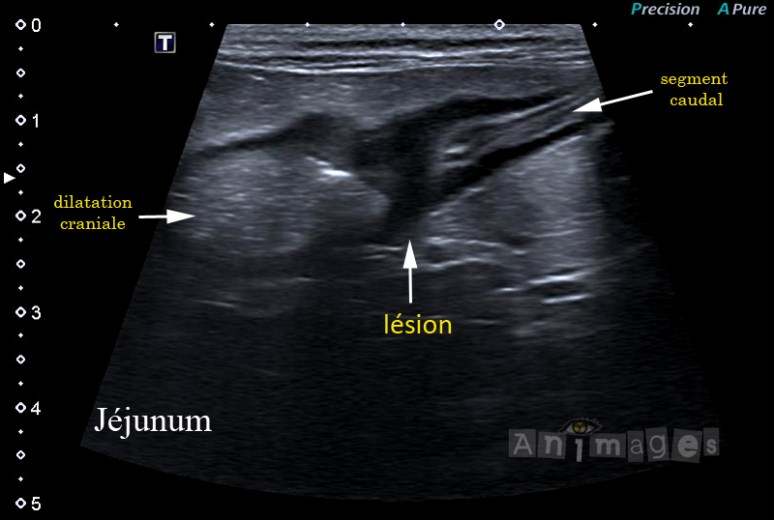

Il était une fois Benoit, un siamois mâle opéré de 11 ans, référé pour une échographie abdominale dans le but d’investiguer une perte d’appétit et une léthargie durant depuis maintenant 3 à 4 semaines, le tout ayant débuté par des vomissements projectiles. Les vomissements persistent depuis. L’examen démontre que Benoit est abattu, déshydraté et inconfortable à la palpation abdominale. Son profil sanguin n’indique alors qu’une légère anémie (HT 27%) avec une légère hausse des bilirubines totales et une légère baisse des protéines totales (alb/glob = 30/26). L’examen échographique de l’abdomen révèle, entre autres, un phénomène obstructif, impliquant le jéjunum, associé à une lésion pariétale focale, circonférentielle et sténosante (image ci-dessous). La paroi affectée est hypoéchogène et il y a perte de distinction de ses couches. Cranialement il y a accumulation d’ingesta (signe du gravier) et hypertrophie de la musculeuse intestinale indiquant ainsi une lésion chronique et progressive. Caudalement l’intestin est vide de contenu. Ces changements sont accompagnés d’une légère lymphadénomégalie régionale.